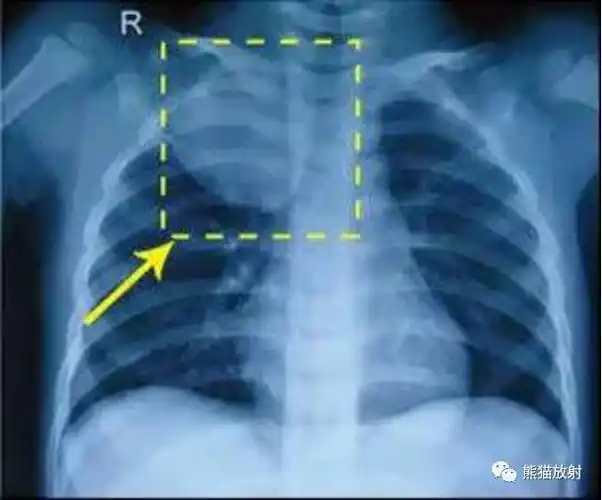

气胸x线胸片图解

拍胸片可见病侧肺明显"压缩"(类似气球漏气瘪掉)及"气胸线",如图:自发